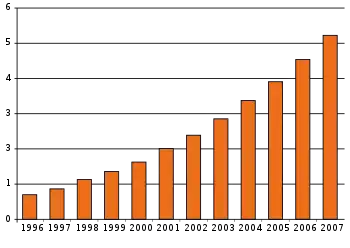

Although intended to increase public confidence in vaccinations, the decision to remove thiomersal instead led to some parents suspecting thiomersal as a cause of autism. This concern over a vaccine-autism link grew from a confluence of several underlying factors. First, methylmercury had for decades been the subject of widespread environmental and media concern after two highly publicized episodes of poisonings in the 1950s and 1960s in Minamata Bay, Japan from industrial waste and in the 1970s in Iraq from fungicide contamination of wheat. These incidents led to new research on methylmercury safety and culminated in the publication of an array of confusing recommendations by public health agencies in the 1990s warning against methylmercury exposure in adults and pregnant women, which ensured a continued high public awareness of mercury toxicity. Second, the vaccine schedule for infants expanded in the 1990s to include more vaccines, some of which, including the Hib vaccine, DTaP vaccine and hepatitis B vaccine, could have contained thiomersal. Third, the number of diagnoses of autism grew in the 1990s, leading parents of these children to search for an explanation for the apparent rise in diagnoses, including considering possible environmental factors.[22] The dramatic increase in reported cases of autism during the 1990s and early 2000s is largely attributable to changes in diagnostic practices, referral patterns, availability of services, age at diagnosis, and public awareness,[35] and it is unknown whether autism's true prevalence increased during the period.[34] Nevertheless, some parents believed that there was a growing "autism epidemic" and connected these three factors to conclude that the increase in number of vaccines, and specifically the mercury in thiomersal in those vaccines, was causing a dramatic increase in the incidence of autism.[22]